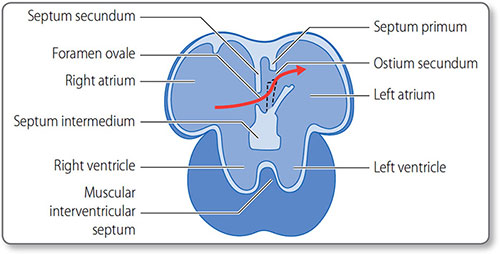

Atrial septation

Atrial septation starts around day 30, when the septum primum descends from the roof of the atrium toward the endocardial cushions. In the fetus, blood shunts through the orifice primum. Once this is obliterated by the fusion of the septum primum and the endocardial cushions, the second ostium develops.

25The septum secundum then develops directly to the right of the septum primum. Both septae have posteroinferior windows that together form the foramen ovale. This flap valve allows right-to-left blood flow (Figure 1.18) and closes when systemic blood pressure increases after birth.

Figure 1.18: Fetal heart circulation. The interatrial septa and the foramen ovale flap valve (black dashed line). The rigid septum secundum grows alongside the septum primum. Fast flowing blood from the ductus venosus is directed across the atrial septae through the foramen ovale flap valve (red arrow). The valve closes after birth due to increased left atrial pressure.